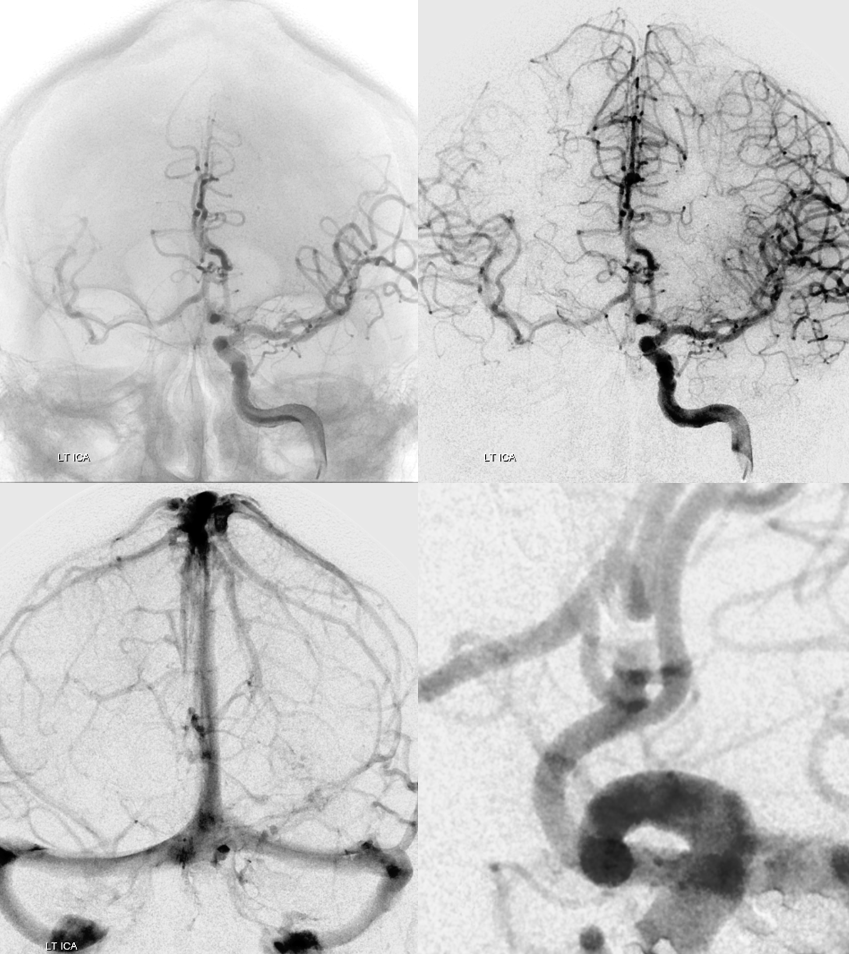

Angio intraop post bypass- STA-MCA working

ACA-ACA did not have flow at this point. Tested by a left A2 BTO. How does that test for bypass patency?

Bypass working even better

PCOM working correspondingly less. Ophthalmic no longer needed

Bilateral CBCT Injections. A big bonus — the ACA-ACA bypass now seems to be patent! Cant see that from 2D images really at this stage. We did not realise this at first but became clear later

A3-A3 bypass more images

Post. Bilateral injections. The right ACA is supplied retrogradely via the ACA-ACA bypass. The MOST important finding here is that there is no longer flow across the ACOM. This is what flow modification is. Changing dynamics to impact aneurysm.